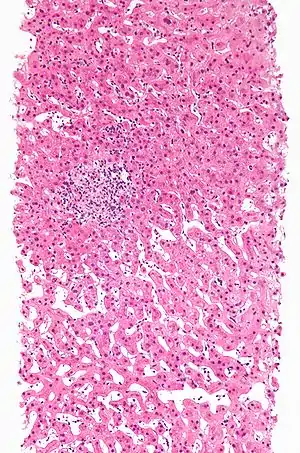

| Drug-induced hepatitis with granulomata. Other causes were excluded with extensive investigations. Liver biopsy. H&E stain. | |

Drug-induced hepatic granulomas are usually associated with granulomas in other tissues and patients typically have features of systemic vasculitis and hypersensitivity. More than 50 drugs have been implicated.

- Causes:

- Allopurinol, phenytoin, isoniazid, quinine, penicillin, quinidine